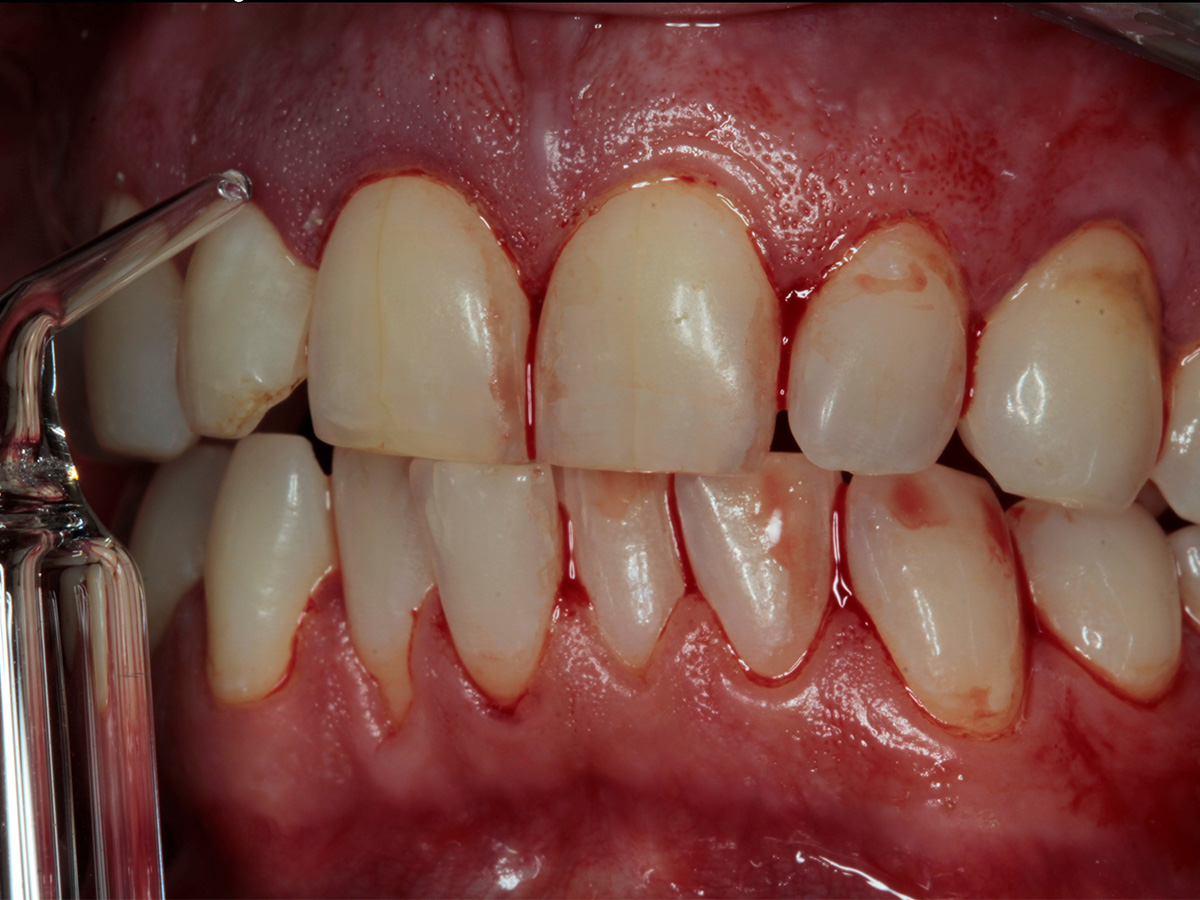

In diesem Workshop erhalten Sie umfassendes Wissen für die Behandlung von Parodontitis-Patientenen. Zunächst führt Sie Yvonne Gebhardt durch moderne subgingivale Behandlungskonzepte – das Herzstück der PA-Therapie. Anschließend erklärt Ihnen Sonja Steinert die faszinierenden Zusammenhänge des Knochenstoffwechsels: Wie Entzündungen den Knochenabbau fördern und wie Sie mit gezielter Therapie und Vitamin D gegensteuern können.

• Subgingivales Behandlungskonzept

• Parodontale Krankheitsbilder erkennen